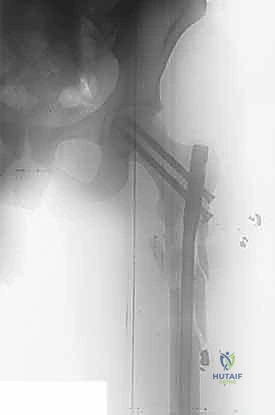

3. التثبيت الداخلي المفتوح (ORIF - Open Reduction and Internal Fixation)

بعد الوصول إلى الكسر وتنظيف المفصل من الشظايا والدم المتخثر، يتم إرجاع القطعة المكسورة لمكانها. يستخدم الدكتور هطيف أحدث التقنيات لتثبيتها:

* مسامير هيربرت أو المسامير الغاطسة (Headless Compression Screws): يتم إدخال هذه المسامير بحيث يغوص رأس المسمار بالكامل تحت مستوى الغضروف المفصلي. هذا يضمن عدم احتكاك معدن المسمار بالتجويف الحقي أثناء الحركة، مما يمنع تدمير المفصل.